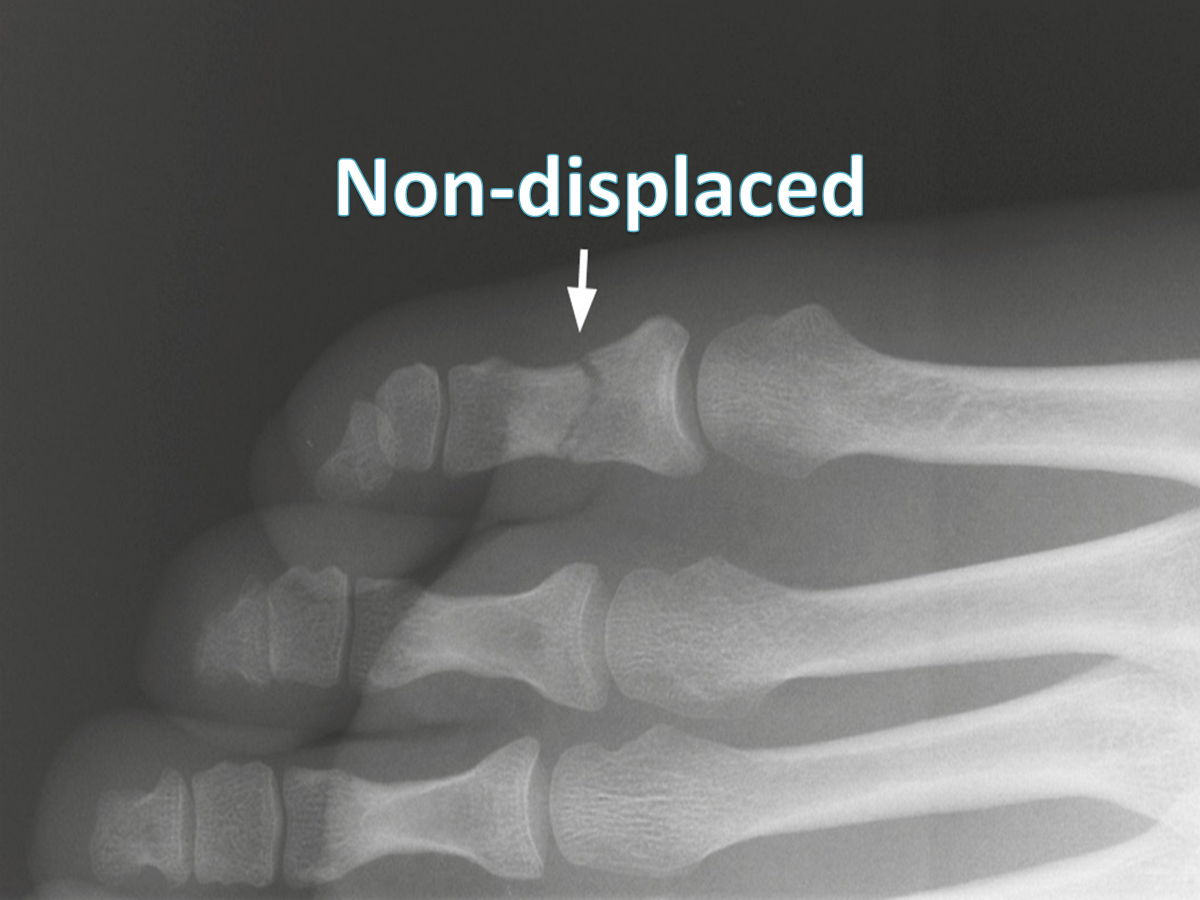

Nondisplaced fractures

a crack or break but the bones stays in its place

nondisplaced fracture